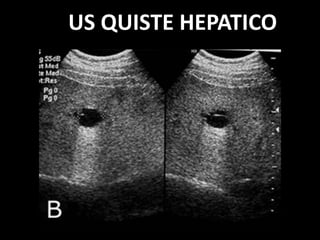

PROCESO CONGENITO: QUISTE

HEPÁTICO

• Quiste simple

• Circular

• Membrana periférica

• Contenido econegativo.

• Refuerzo posterior.

US QUISTE HEPATICO